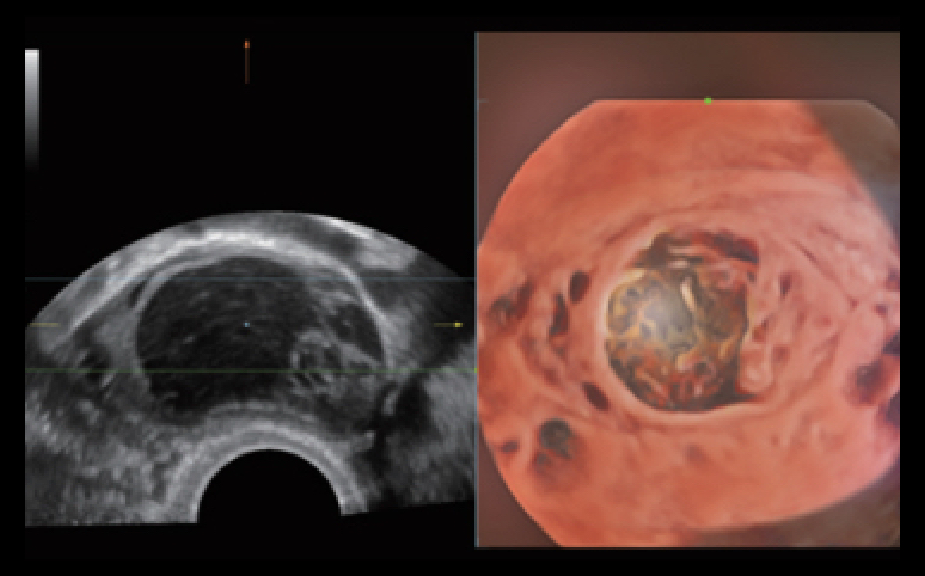

Gambar Klinis

Transduser